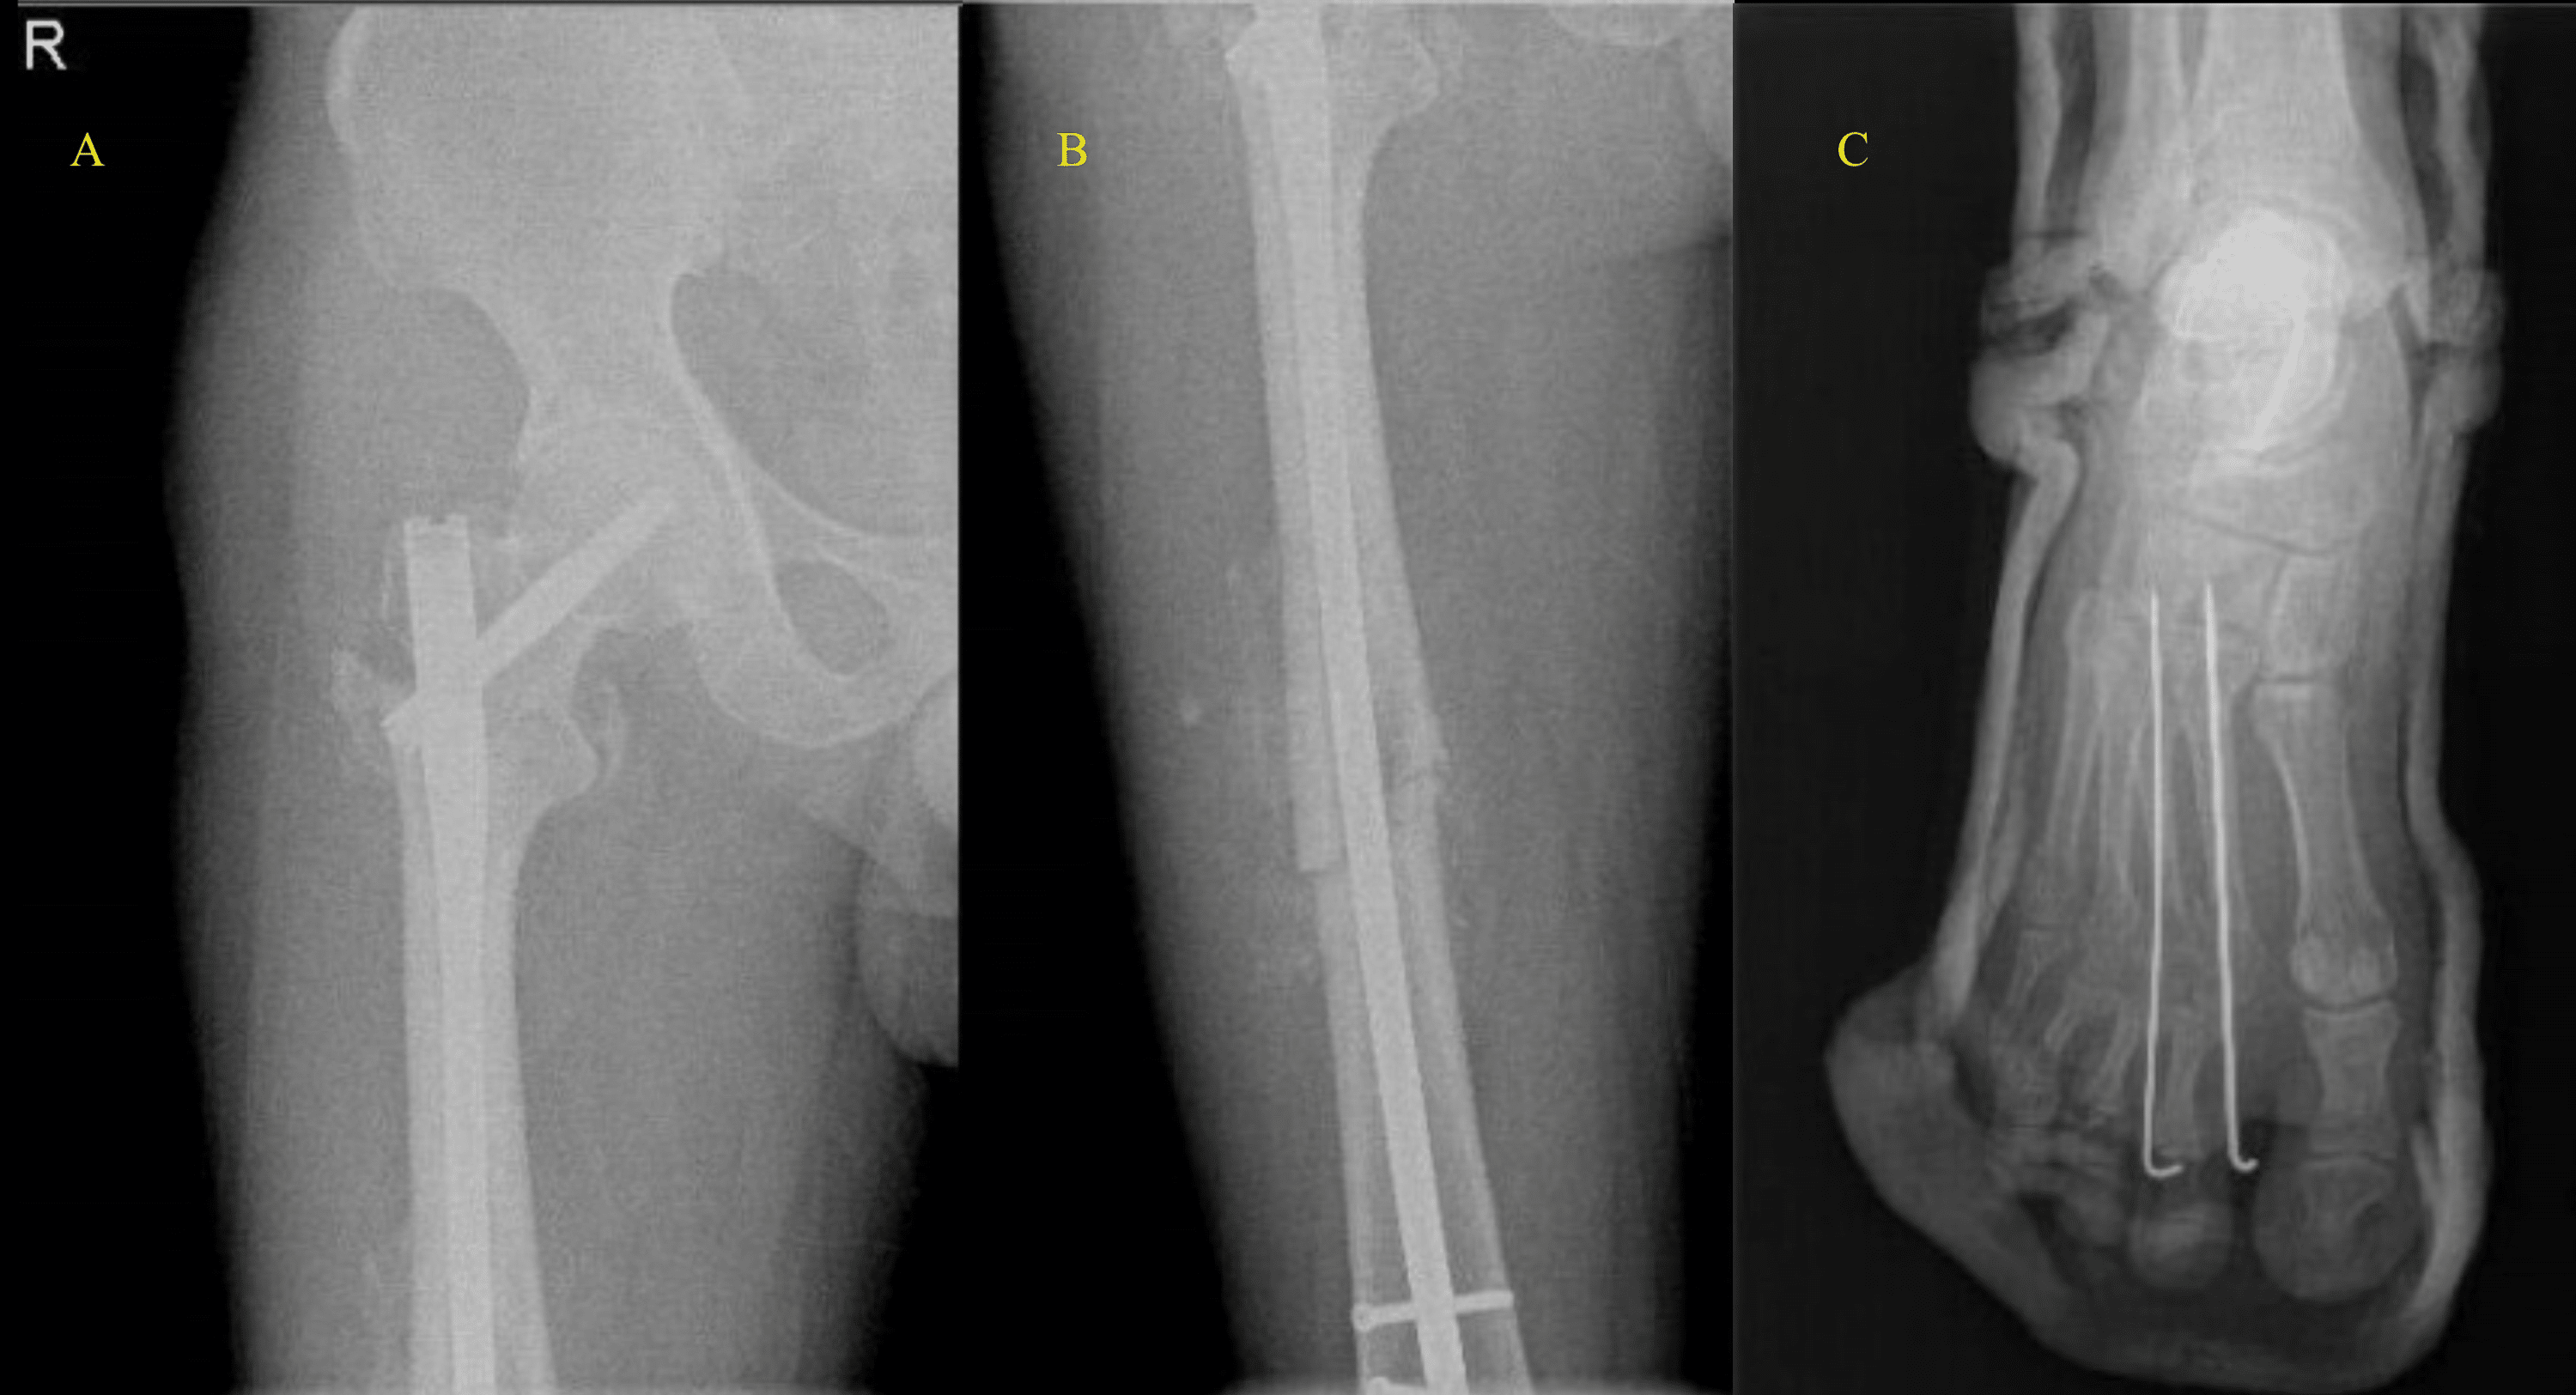

From www.researchgate.net

Evidence of fracture healing of the right femur fracture (A,B) and the... Download Scientific Zometa Femur Fracture Although the benefit of preventing osteoporotic fractures greatly outweighs the risk of atypical fracture in bisphosphonate users, concern about atypical fracture risk has led to a decrease in bisphosphonate use. Zoledronic acid, in combination with calcium and vitamin d, will reduce the risk of vertebral fractures, and to a lesser extent, hip. We found that the risk of atypical femur. Zometa Femur Fracture.